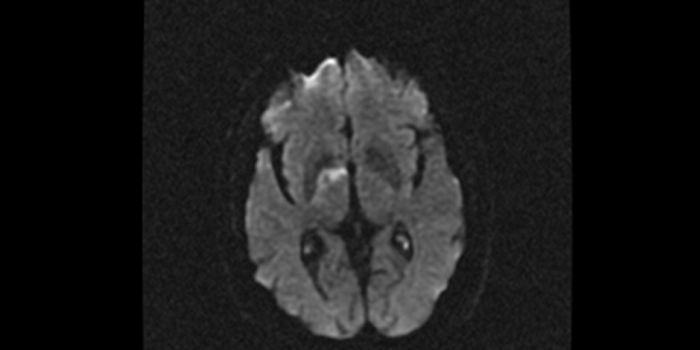

JAN 01, 2021CardiologyScientists have been trying to determine if the SARS-CoV-2 virus infects brain cells directly, or if the virus severely ...

MAY 18, 2017Health & MedicineWhile current guidelines for acute stroke treatment indicate that removing brain clots should only be done within six ho ...

FEB 13, 2015NeuroscienceWhile tens of millions of people have abnormal, leak-prone sproutings of blood vessels in the brain called cerebral cave ...